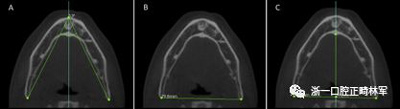

使用CS 3D成像軟件(版本3.4.3; Care-stream Health,Rochester,NY)進(jìn)行線性和角度測量。線性指標(biāo)包括鼻前后棘間距(ANS-PNS距離),咽腔最短距離(最短距離),咽腔C1的前后距離(APC1),咽腔C1的側(cè)壁間距離(LLC1),咽腔C2的前后距離(APC2),咽腔C2的側(cè)壁間距離(LLC2),咽腔C3的前后距離(APC3),咽腔C3的側(cè)壁間距離(LLC3),咽腔-會厭基底的前后距離(AP會厭),咽腔-會厭基底的側(cè)壁間距離(LL會厭),下頜骨兩側(cè)間的距離(L下頜骨),下頜骨的前后距離(AP下頜骨),舌骨兩側(cè)間的距離(L1舌骨)以及舌骨的前后距離(AP舌骨)。下頜骨前后角度的測量(下頜AP角),下頜橫角(TA下頜骨)和舌骨橫角(TA舌骨)。測量結(jié)果列于表I和圖1-4中。

圖3.A,舌骨橫角; B,LL舌骨; C,AP舌骨。